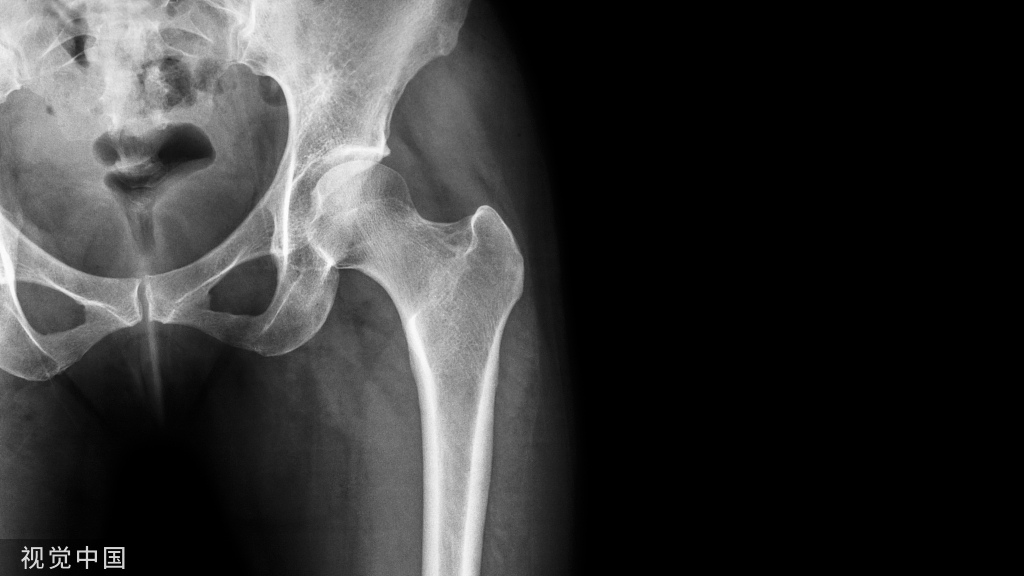

病史:男孩,8岁,外伤来诊,发现左侧坐骨异常;

左侧坐骨锯齿状改变,骨折?

X线:骨盆正位片为常规检査。在患侧坐骨耻骨结合处可见到骨皮质膨隆,有时出现层状改变,膨隆部位密度浓淡不均,中央可见类圆形透光区,偶有骨皮质破裂影像,膨隆周围可见硬化改变。